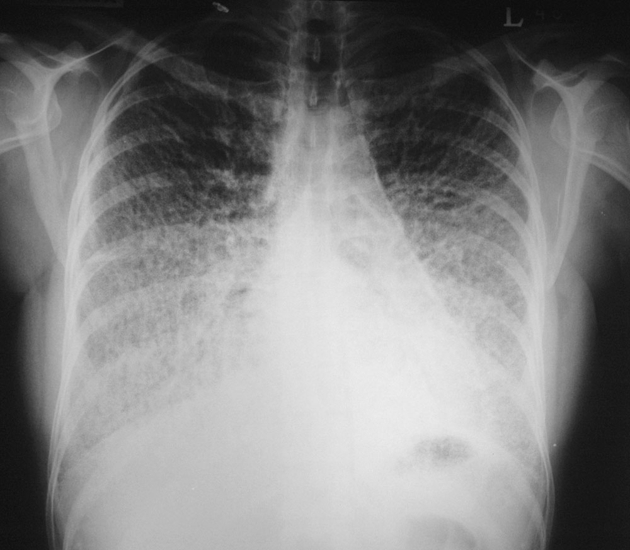

CXR: Hyperdense Nodules DDx

Healed Varicella Pneumonia

DDx: